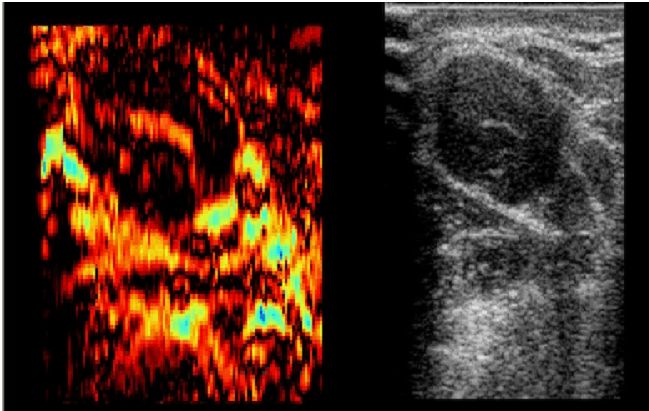

Echtzeit Elastographie: in vivo Lymphknoten Sample 01 (jpg)

Echtzeit Elastographie: in vivo Lymphknoten Sample 02 (jpg)